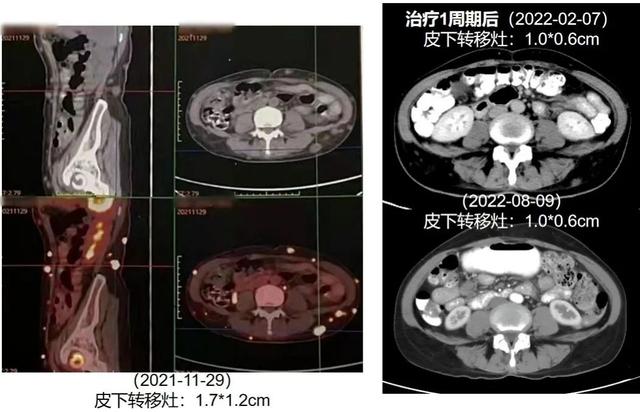

2022年1月7日,患者开始接受达拉非尼(150mg bid)+曲美替尼(2mg qd)一线治疗,联合双磷酸盐抗骨代谢治疗。治疗1周期(2022年2月7日)后,肝转移灶、脾转移灶和皮下转移灶缩小,肾盂转移灶消失。最新复查结果(2023年1月4日)显示,肝转移灶、脾转移灶稳定控制,病情持续控制中。

图4. 治疗前后肾盂转移灶变化

图5. 治疗前后皮下转移灶变化